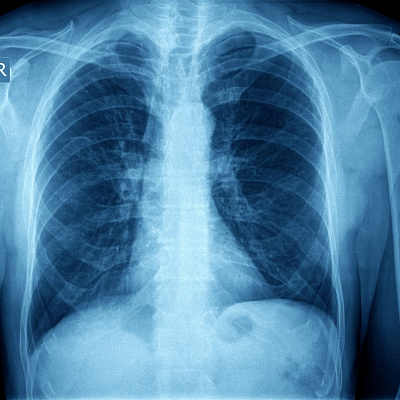

Золотым стандартом диагностики по клиническим рекомендациям является рентгенография органов грудной клетки. Отсутствие легочного рисунка, четкий край спавшейся анатомической структуры позволяет точно выставить диагноз. Определить тактику лечения.